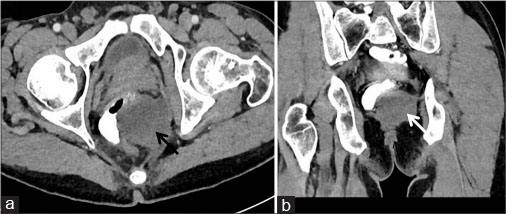

A 63-year-old-male patient presented with on and off constipation for the past 3 months. The patient was chronic smoker for 20 years. Per rectal examination revealed solitary palpable mass along posterior rectal wall extending from 4 to 8 o’clock position. Patient’s blood counts, viral markers, and chest X-ray were normal. With a suspicion of rectal malignancy, triphasic contrast-enhanced CT abdomen was performed. CECT revealed heterogeneous predominantly exophytic mass lesion abutting the rectum [Figure 1]. On histopathological examination, the specimen revealed fibrocollagenous cores with a cellular spindle cell tumor comprising of spindle cell. On immunohistochemistry, tumor cells were strongly positive for CD34 and CD117 [Figure 2]. Postimatinib therapy, the tumor showed a significant reduction in size, attenuation, and internal neovascularity [Figure 3].

| Figure. 1 (a and b) Pretreatment imaging. Axial and coronal reformatted computed tomography images showing heterogeneously hyperenhancing exophytic mass lesion arising from rectum (arrows)